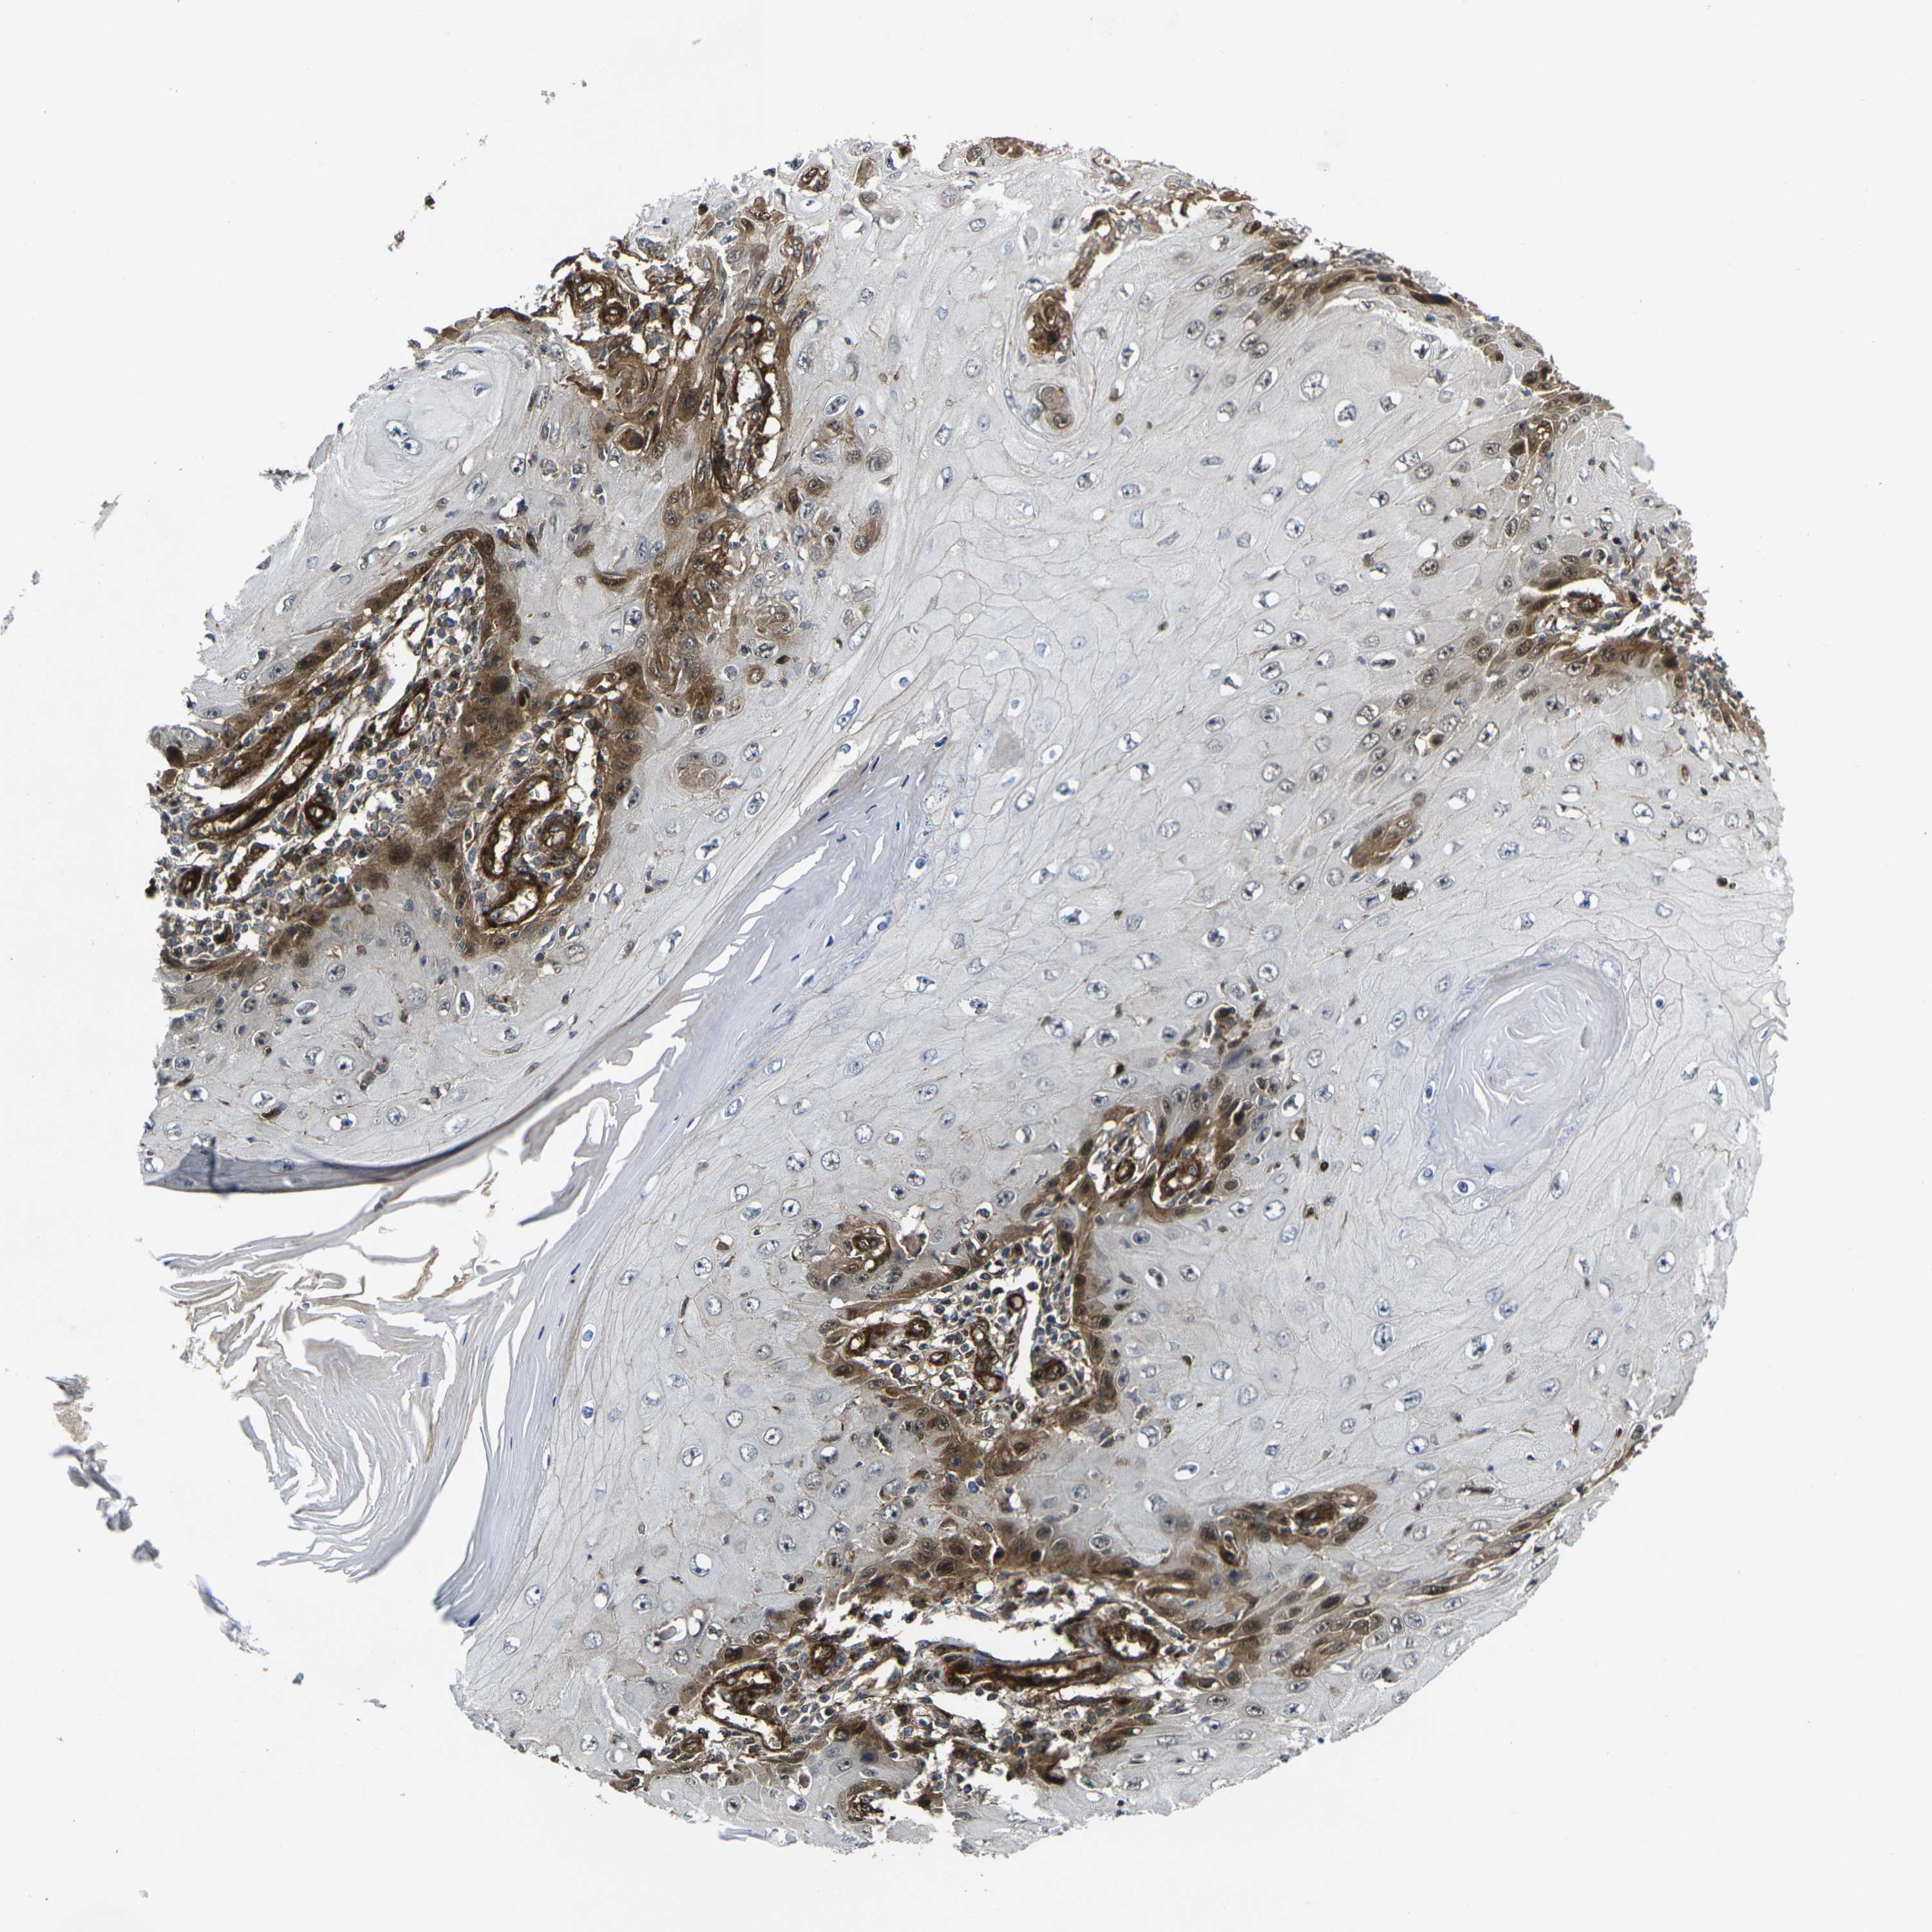

Basal cell and squamous cell cancer

SKIN CANCER - Protein expressioni

A mouse-over function shows sample information and annotation data. Click on an image to view it in a full screen mode. Samples can be filtered based on level of antibody staining by selecting one or several of the following categories: high, medium, low and not detected. The assay and annotation is described here.

Antibody stainingi

Antibody staining in the annotated cell types in the current human tissue is reported as not detected, low, medium, or high, based on conventional immunohistochemistry profiling in selected tissues. This score is based on the combination of the staining intensity and fraction of stained cells.

Each image is clickable and will lead to virtual microscopy that enables deeper exploration of all samples and also displays staining intensity scores, fraction scores and subcellular localization as well as patient and tissue information for each sample.

Antibody HPA001490

Antibody HPA013616

Staining

High

Medium

Low

Not detected

Intensity

Strong

Moderate

Weak

Negative

Quantity

>75%

75%-25%

<25%

None

Location

Nuclear

Cytoplasmic/membranous

Cytoplasmic/membranous,nuclear

Squamous cell carcinoma, NOS

Basal cell carcinoma